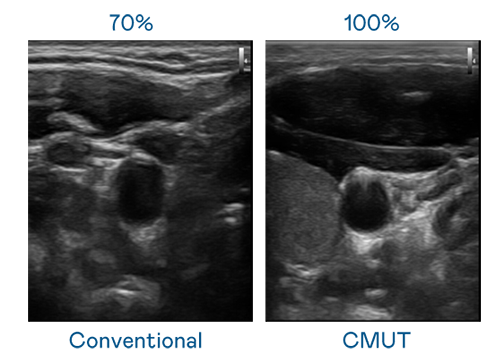

CMUT 技术是一种用电容式微机电元件来产生超音波讯号的技术。与传统 PZT 压电式技术相比,CMUT 频宽增加 30%,更宽频的超音波讯号让影像解析度大幅提升,是实现高影像品质医疗超音波扫描、促进精准医疗发展的关键技术。

大频宽带来超清晰影像

超音波影像的解析度高低,首先取决于探头能发出的讯号频宽。DB旗舰 CMUT 可提供高清晰的超音波讯号,提供高频宽、高灵敏度、影像纹理细节更高的超音波影像,协助医护人员缩短影像判读时间及利用精准的医疗影像进行诊断。